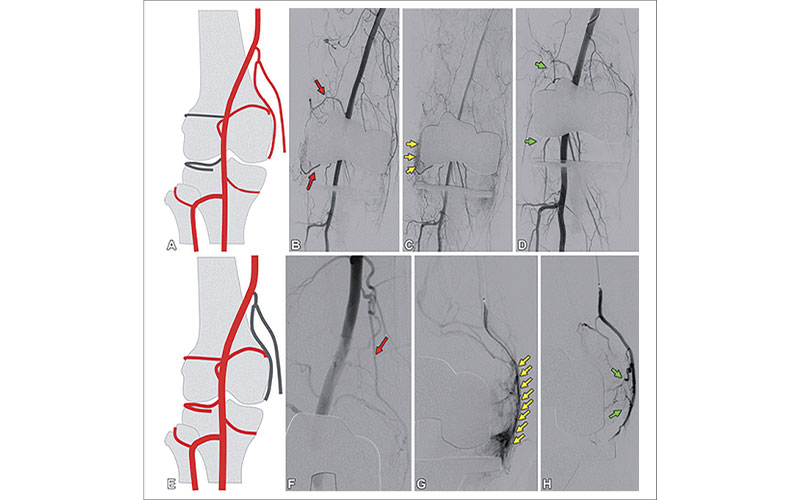

GAE for hemarthrosis. (A) Drawing shows the anatomy of superior and inferior lateral GAE. (B–D) Angiograms in a patient with hemarthrosis that were obtained after TKA but before embolization (B, C) demonstrate prominent superior and inferior lateral geniculate arteries (red arrows) and synovial blush (yellow arrows) associated with prominent arteries. Angiogram obtained after particle and coil embolization (green arrows) (D) demonstrates nonfilling of the lateral genicular branches and loss of synovial blush. (E) Drawing demonstrates the anatomy of descending GAE. (F–H) Angiogram in a patient with hemarthrosis from hemophilia that was obtained before embolization (F) demonstrates the descending geniculate artery (red arrow) contributing to significant synovial blush. Angiogram obtained after injection with a microcatheter within the descending geniculate artery (G) shows synovial enhancement (yellow arrows) along the medial aspect of the knee. Angiogram obtained after particle embolization (H) demonstrates reduction in synovial blush (green arrows).

Heller et al, RadioGraphics 2022; 42;289-301 ©RSNA 2022